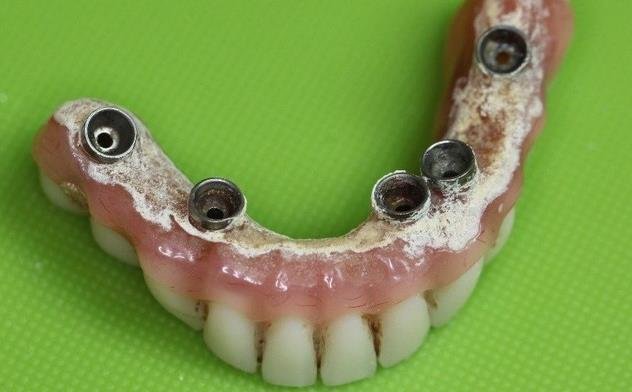

尼種修復方案之後,對患者來講,日常清潔好關鍵,因為尼種架橋唔好清潔,長期就會出現↓:

咁就好易引起種植牙發炎,導致失敗!而且尼種架橋修復一單有一顆壞咗,整排牙都唔可以用,所以大家做全口修復陣時,一定要結合醫生建議谂清楚,不過好多醫生可能為咗賺錢都會迴避尼個問題。